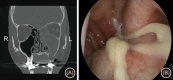

Methods: Two latex-injected cadaveric specimens were utilized to perform surgical dissections to demonstrate different approaches to the MS. The procedures were documented with macroscopic images and endoscopic pictures.

Results: Dissections were performed to approach the MS medially (endoscopic maxillary antrostomy and ethmoidectomy), anteriorly (Caldwell-Luc), superiorly (transconjunctival/transorbital approach), inferiorly (transpalatal approach), and posterolaterally (preauricular hemicoronal approach).